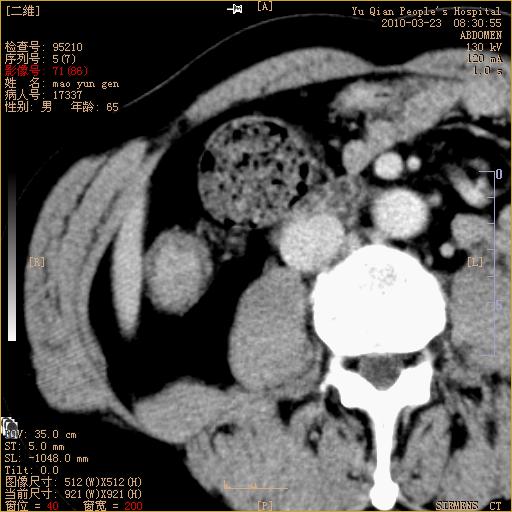

标题: CT25266:消瘦月余,前来肝部检查,请看看肠腔 [打印本页]

标题: CT25266:消瘦月余,前来肝部检查,请看看肠腔

肝区结肠占位,腺癌可考虑,建议肠镜活检。

升结肠肠壁增厚,不均强化,考虑升结肠腺癌可能性,建议肠镜检查。

1)考虑升结肠癌。2)右肾小囊肿。